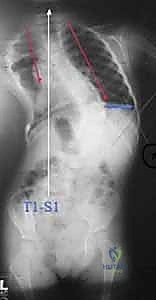

- الأشعة السينية (X-rays) البانورامية: يتم أخذ صور للعمود الفقري بالكامل من الأمام والخلف والجانب (أثناء وقوف الطفل أو جلوسه إذا كان لا يستطيع الوقوف). يتم من خلالها قياس "زاوية كوب" (Cobb Angle) لتحديد شدة الانحناء.

الفكرة العبقرية وراء قضبان النمو هي "التثبيت دون الدمج". يقوم الدكتور هطيف بتثبيت العمود الفقري من الأعلى (عند الفقرات الصدرية العليا) ومن الأسفل (عند الفقرات القطنية أو الحوض) باستخدام مسامير أو خطاطيف تيتانيوم. يتم توصيل هذه المثبتات بقضبان معدنية قوية تمتد عبر منطقة الجنف.

الجزء الأهم: لا يتم دمج (تلحيم) العظام في المنطقة الوسطى المنحنية. هذا يسمح للعمود الفقري بالاستمرار في النمو. مع نمو الطفل، يتم "إطالة" هذه القضبان بشكل دوري لمواكبة زيادة طول الطفل وتصحيح الانحناء تدريجياً.

- التصحيح الأولي: يتم ربط القضبان بالمسامير، ويتم إجراء تصحيح أولي آمن للجنف، مع التأكد من إشارات جهاز المراقبة العصبية.